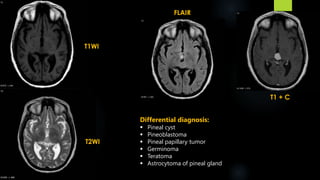

FLAIR

T1 + C

T1WI

T2WI

Differential diagnosis:

 Pineal cyst

 Pineoblastoma

 Pineal papillary tumor

 Germinoma

 Teratoma

 Astrocytoma of pineal gland

 Pineocytoma